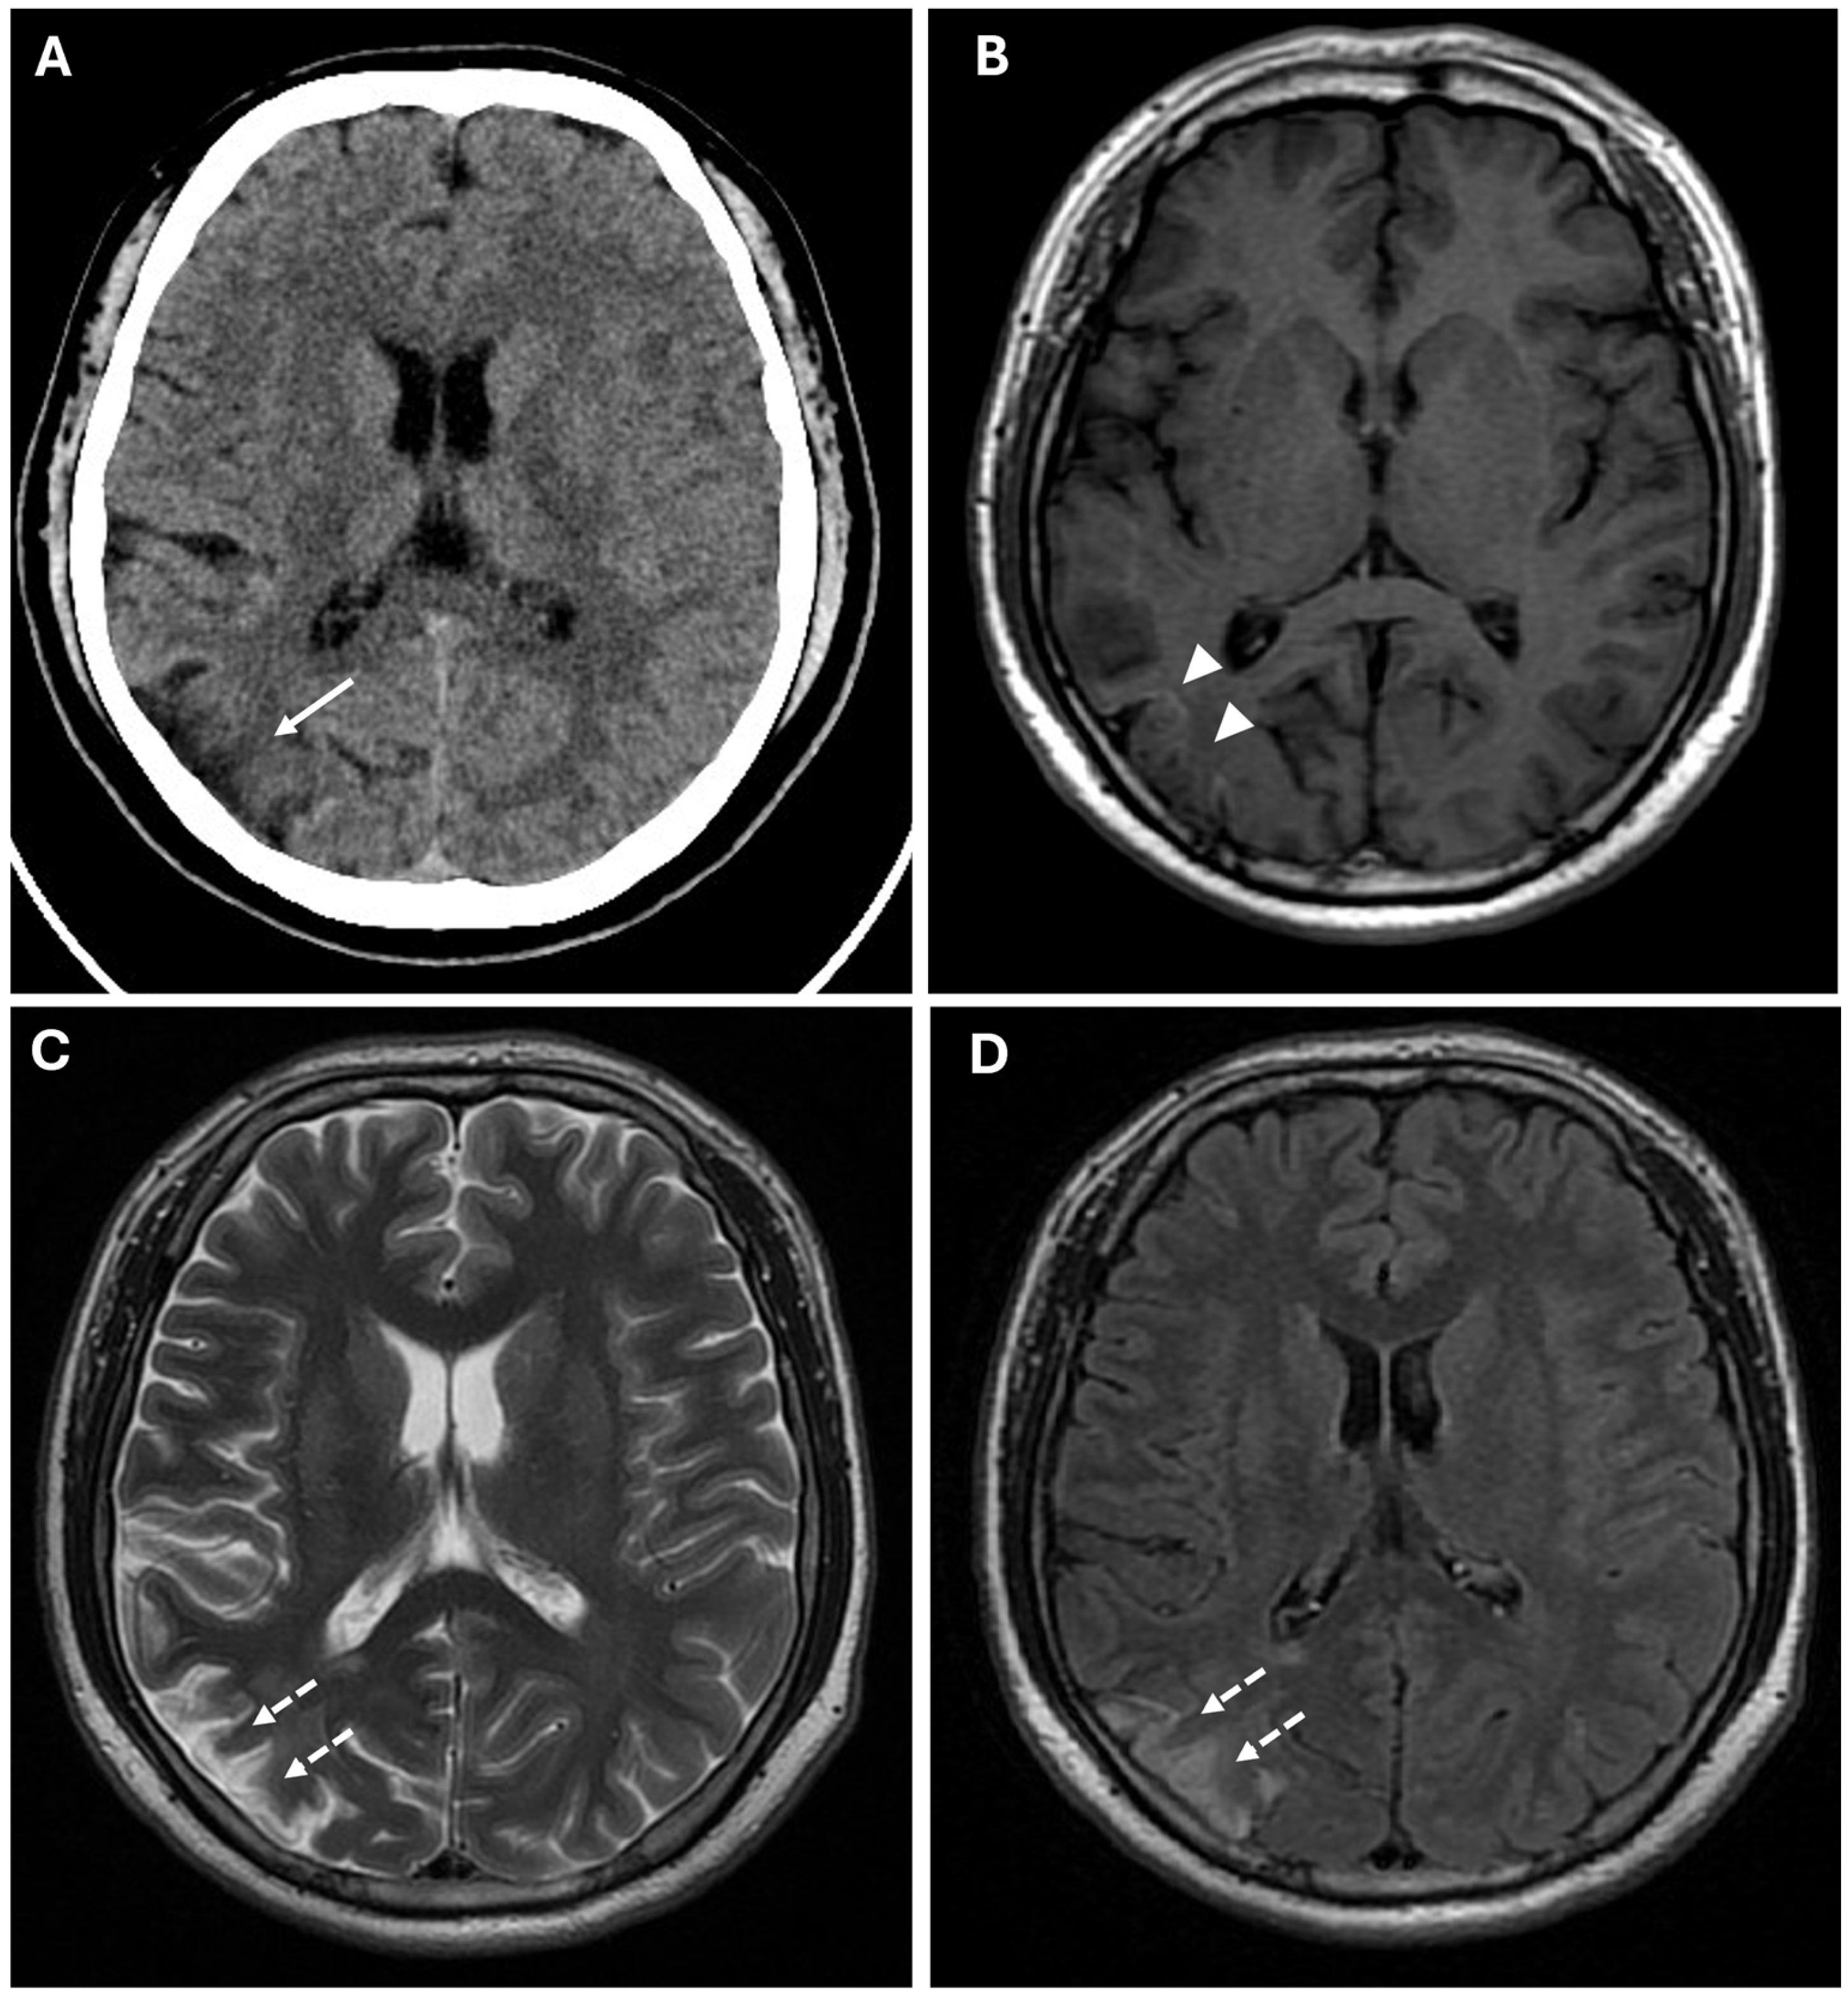

CT findings raised the suspicion of vaso-occlusive disease, and, in particular, moyamoya disease; to exclude secondary causes of moyamoya disease, the following parameters were also evaluated: autoimmune panel (ANA, ENA, anti-dsDNA, and ANCA), thyroid function and antibodies (TSH, FT3, FT4, and anti-TPO), infectious screening (HBV, HCV, HIV, and syphilis), and thrombophilia panel; all of these parameters showed normal values. Subsequently, the patient underwent MRI, MRA, and DSA examinations. MR examination (performed with a Signa HDxT MR scanner, GE Healthcare, Milwaukee, WI, USA) showed the presence of hyperintense areas on T2-weighted and FLAIR sequences, with true restricted diffusion (increased signal on DWI sequences and reduced ADC values), located in right prefrontal, superior frontal, and postcentral gyrus; in the right periventricular and supraventricular white matter; and at the level of the splenium of the corpus callosum (Figure 1); the cerebral cortex also showed a swollen appearance in these regions, confirming recent ischemic lesions. A small hypointense area on T2*-weighted sequences was also identified at the level of the aforementioned altered signal area of the right supraventricular white matter. This area was also hyperintense on T1-weighted sequences, indicating a subacute hemorrhagic lesion. Moreover, chronic ischemic lesions, characterized by hyperintensity on T2-weighted and FLAIR sequences, with no diffusion restriction, were detected in the right parietal, occipital, and temporal cortico-subcortical regions (Figure 3).

Figure 3. Chronic ischemic lesions. (A) A non-enhanced CT image in axial view shows a hypodensity area in the right frontal and parietal lobes with atrophic brain cortex (white arrow). (B) Axial T1-weighted spin echo sequence shows mild linear hyperintensity in the right parietal lobe, coherent with cortical laminar necrosis (white arrowheads). (C,D) Axial T2-weighted (C) and FLAIR (D) sequences show right parietal and periventricular areas of hyperintensity compatible with subacute-chronic ischemic lesions (white dotted arrows).